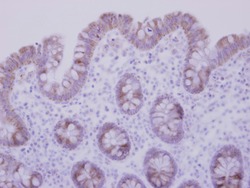

Supportive validation

- Submitted by

- Signalway Antibody LLC (provider)

- Main image

- Experimental details

- Immunohistochemical analysis of paraffin-embedded Normal Colon, using CCDC83 antibody at 1: 500 dilution.